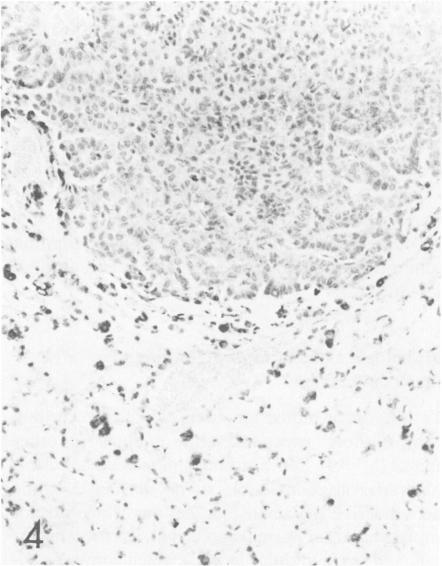

The localization of surfactant apoprotein (SAP) and the Clara cell antigen(s) (CCA) was studied in naturally occurring and experimentally induced pulmonary hyperplasias and neoplasms by avidin-biotin peroxidase complex (ABC) immunocytochemistry. Lungs of B6C3F1 and A strain mice with naturally occurring lesions, B6C3F1 mice given injections of N-nitrosodiethylamine (DEN), BALB/c nu/nu or nu/+ mice exposed transplacentally on Day 16 of gestation to ethylnitrosourea (ENU), or BALB/c nu/+ mice exposed to ENU at 8-12 weeks of age were preserved in formalin or Bouin's fixative. After ABC immunocytochemistry, SAP was found in the cytoplasm of normal alveolar Type II cells; in the majority of cells in focal alveolar and solid hyperplasias originating in peribronchiolar or peripheral locations; and in solid, tubular, papillary, and mixed adenomas and carcinomas. The larger mixed-pattern neoplasms and small or large tubular neoplasms usually had the least number of cells with SAP. The majority of large papillary adenomas and carcinomas in BALB/c mice exposed to ENU and in untreated A strain mice contained SAP in the nuclei of many neoplastic cells but only in the cytoplasm of a few neoplastic cells. CCA was found in normal Clara cells of bronchi and bronchioles but not in any hyperplastic or neoplastic lesion of any mouse studied. This study provided immunocytochemical evidence that the vast majority of naturally occurring and experimentally induced pulmonary neoplasms of mice are alveolar Type II cell adenomas and carcinomas.

采用抗生物素蛋白-生物素过氧化物酶复合物(ABC)免疫细胞化学方法,研究了表面活性物质载脂蛋白(SAP)和克拉拉细胞抗原(CCA)在自然发生和实验诱导的肺增生及肿瘤中的定位。对患有自然病变的B6C3F1和A品系小鼠、注射N-亚硝基二乙胺(DEN)的B6C3F1小鼠、在妊娠第16天经胎盘暴露于乙基亚硝基脲(ENU)的BALB/c裸鼠或裸+/+小鼠,或在8-12周龄时暴露于ENU的BALB/c裸+/+小鼠的肺组织,用福尔马林或布因氏固定液保存。经过ABC免疫细胞化学检测,发现SAP存在于正常肺泡II型细胞的细胞质中;存在于起源于细支气管周围或周边部位的局灶性肺泡增生和实性增生的大多数细胞中;也存在于实性、管状、乳头状和混合性腺瘤及癌中。较大的混合型肿瘤和小或大的管状肿瘤中通常含SAP的细胞数量最少。在暴露于ENU的BALB/c小鼠和未经处理的A品系小鼠中的大多数大乳头状腺瘤和癌,在许多肿瘤细胞的细胞核中含有SAP,但仅在少数肿瘤细胞的细胞质中含有。在支气管和细支气管的正常克拉拉细胞中发现了CCA,但在所研究的任何小鼠的增生性或肿瘤性病变中均未发现。本研究提供了免疫细胞化学证据,表明小鼠中绝大多数自然发生和实验诱导的肺肿瘤是肺泡II型细胞腺瘤和癌。